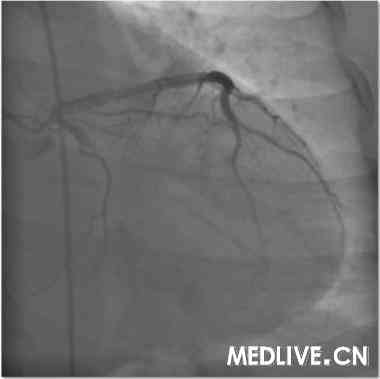

冠造结果(图2-4):回旋支中段100%闭塞;右冠中段100%,并见大量血栓影;前降支中段不规则狭窄50%。结合临床,考虑右冠为急性心肌梗死相关冠脉,应首先对其进行急诊介入治疗。

经右股动脉途径,6F,JR4.0引导管,HT BMW Universal引导丝顺利通过右冠闭塞病变部位,Diver血栓抽吸导管于病变部位及其近、远段部位连续抽吸,反复5次,造影可见右冠血流恢复,余狭窄最重部位直接植入Excel支架3.5*14mm,12atm释放,16atm原位后扩张,最重效果满意,右冠TIMI血流3级(图5-7)。